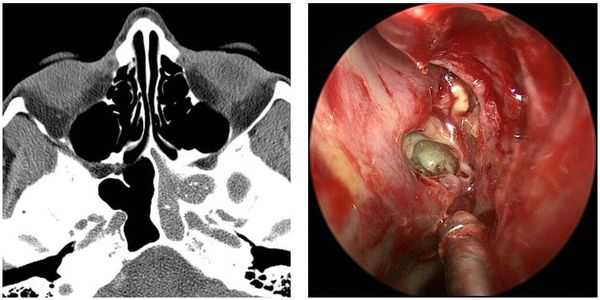

Эндоскопия носовой полости предназначена для рассмотрения аномалий строения структур носа и состояний выводных соустий, а также для проверки на присутствие полипов и иных образований в носовой полости.

Компьютерная томография (КТ) считается одним из наиболее информативных методов диагностики при ХС, целью которого являются:

- установление характера и распространённости патологических процессов;

- выявление причин и индивидуальных особенностей анатомии носовой полости и пазух носа, способствующих рецидиву синусита;

- визуализирование структур, которые не просматриваются при рентгенографии (особенность КТ с высоким разрешением).

- Эндоскопия носа. Диагностика показана для детального осмотра слизистой носоглотки и придаточных пазух, оценки состояния решетчатой воронки и отверстия клиновидной пазухи. С помощью эндоскопической визуализации исключаются опухолевые образования носа.

- КТ околоносовых пазух. По результатам компьютерной томографии определяется конкретный вид синусита, степень пораженности назальных синусов, наличие деформаций и других осложнений хронического воспалительного процесса.